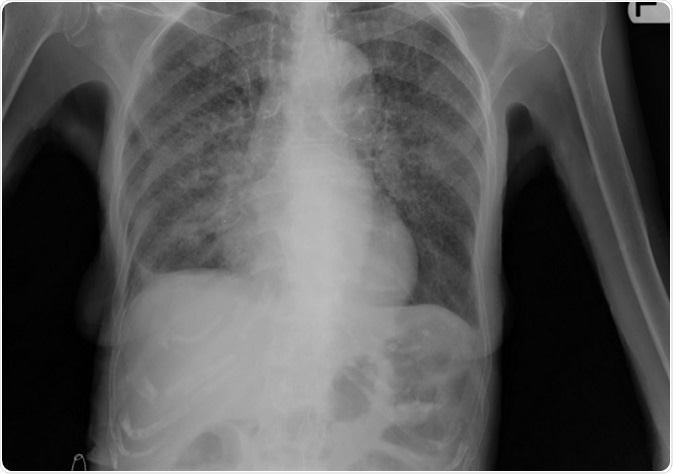

Image: Lung X-ray of patient with tuberculosis. Credit: Yale Rosen/ flickr.com. Shared under the license.

In this type of tuberculosis the lesion more often than not lies in the lungs. A Chest X ray shows the lesion within the lungs. There may be scarred appearance of the lungs.

Primary tuberculosis usually appears in the central upper portion of the lungs with a pleural effusion or collection of fluid around the lungs. In severe disease there may be a picture like millet seeds over the X ray plate of the lungs. This is called milliary tuberculosis.